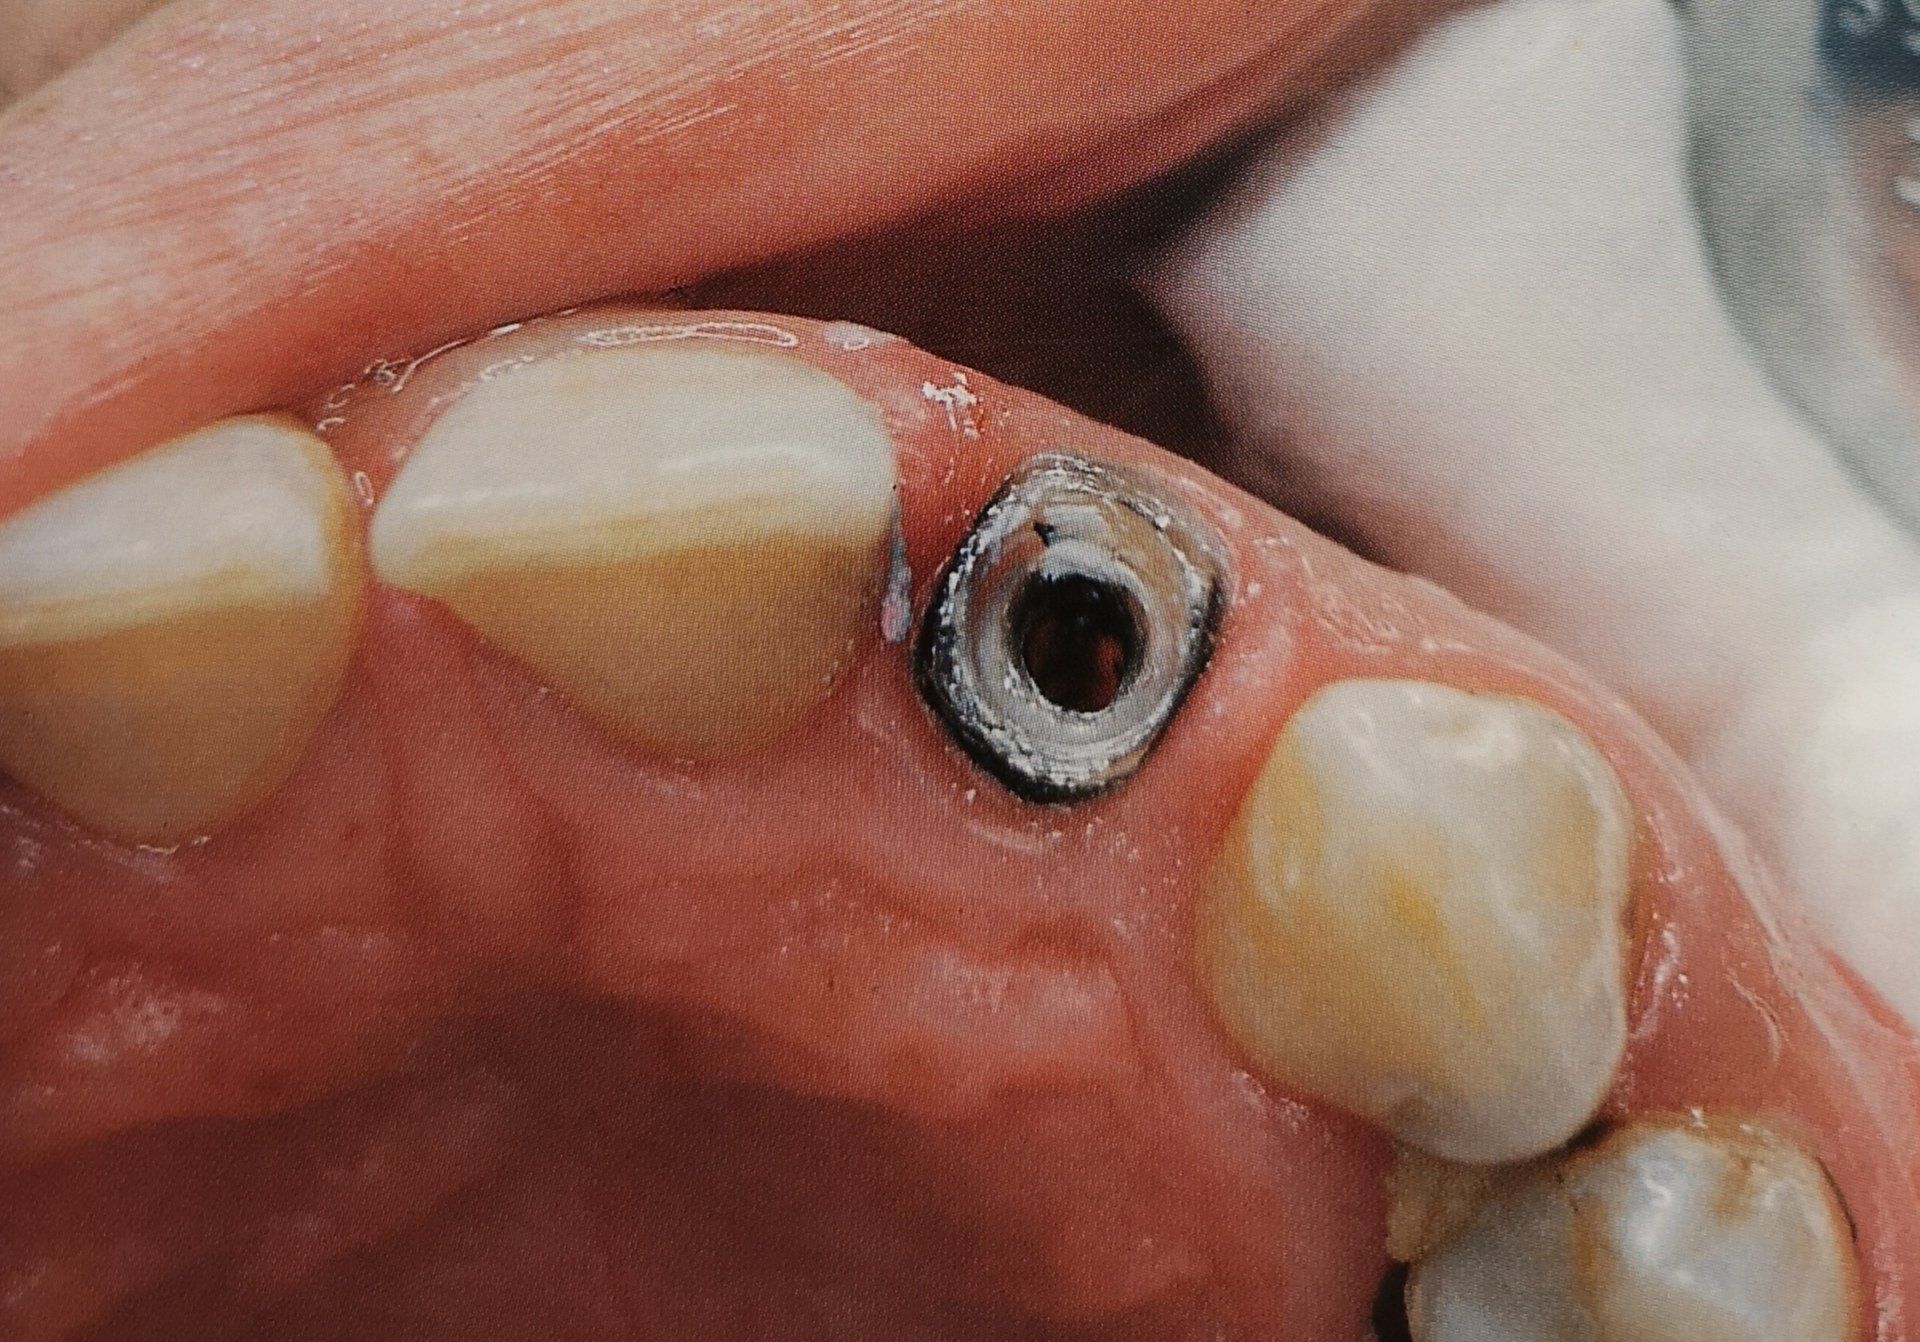

L’endodonzia si occupa della diagnosi e del trattamento dei problemi della polpa dentale, cioè la parte interna del dente, il trattamento più comune è la devitalizzazione, necessaria quando la polpa è infiammata o infetta a causa di carie profonde, traumi o lesioni.

L’endodonzia è la branca dell’odontoiatria che si occupa della cura della polpa dentale, ossia la parte più interna del dente dove si trovano i nervi e i vasi sanguigni.

Un trattamento endodontico, comunemente chiamato devitalizzazione, è necessario quando la polpa si infiamma o si infetta a causa di carie profonde, traumi, o infiltrazioni batteriche.

La Dott.ssa Lombardi interviene rimuovendo il tessuto infetto, disinfettando accuratamente i canali radicolari e sigillandoli, permettendo così di salvare il dente naturale e di evitare l’estrazione.